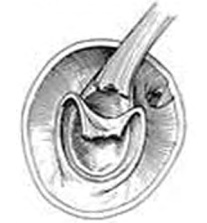

Um paciente nadador profissional, com dor crônica em ombro esquerdo e teste de O’Brien positivo, foi submetido a RNM. A reconstrução tridimensional foi esquematizada na figura apresentada.

A respeito desse caso clínico, é correto afirmar que se trata de uma lesão SLAP do tipo